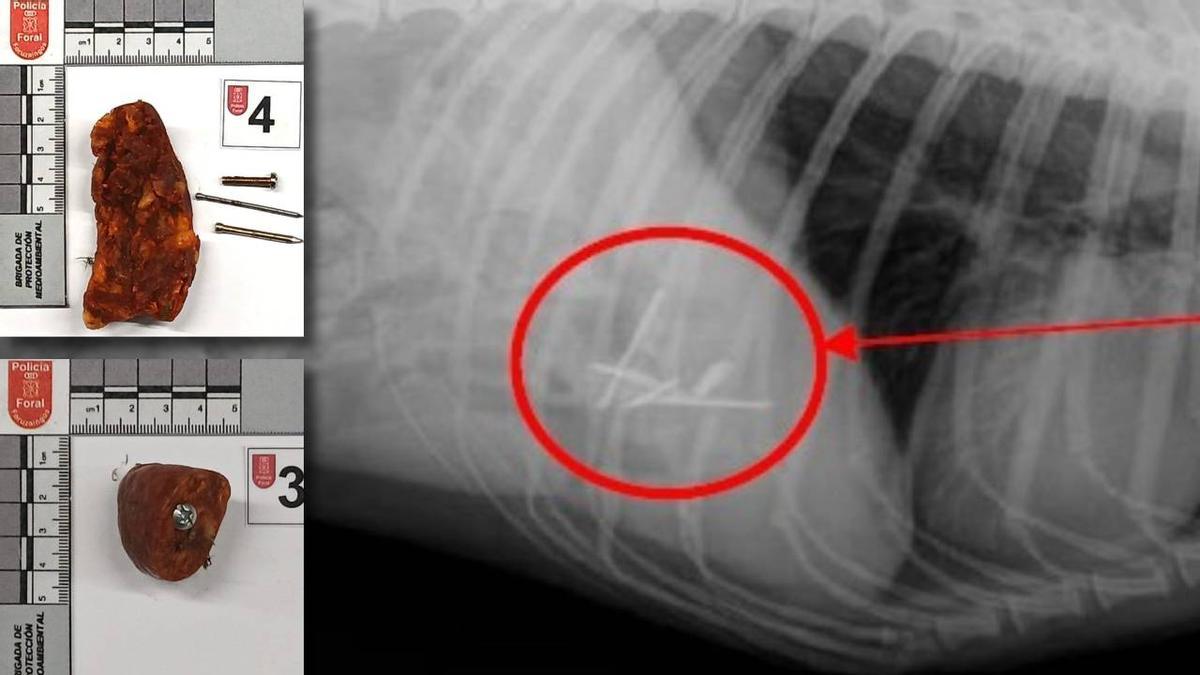

Los hechos se remontan al pasado mes de marzo, cuando se recibió un aviso a través del Centro de Mando y Coordinación (CMC) de Policía Foral alertando sobre la presencia de objetos peligrosos para los animales en la vía pública. Los agentes de la División de Prevención y Atención Ciudadana, desplazados al lugar, localizaron un primer cebo de chorizo con elementos punzantes. Posteriormente, tras una inspección exhaustiva de una zona verde arbolada, hallaron otros tres cebos de idénticas características.

Como consecuencia de estos hechos, una perra ingirió uno de los cebos. Tras ser trasladada a un centro veterinario, las pruebas radiográficas confirmaron la presencia de cuatro clavos en su tracto digestivo. El animal tuvo que ser sometido a una intervención quirúrgica de urgencia para salvar su vida y actualmente se encuentra bajo un protocolo de recuperación.